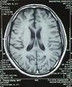

腦白質病合併腦萎縮的CT表現腦白質病的影像學檢測手段中,加權磁共振成像是首選檢查手段,是鑑別早期或輕微腦白質病與精神疾病的重要手段,而CT僅能顯示重度腦白質損害。

3、MRI(磁共振)診斷

MRI是顯示腦白質及白質病灶最敏感的方法,以T2加權像更為敏感。除橫斷位外,還應包括冠狀斷掃描,有些病理變化僅在冠狀斷T2加權像上才能充分顯示。T2加權像顯示的髓磷脂沉積過程與屍檢切片髓磷脂染色所見,相關良好。在矢狀斷像上,MRI可顯示腦幹腦白質的發育情況。若常規掃描發現腦白質信號異常,可行增強掃描,以確定病灶的嚴重程度、活動性和進行鑑別診斷。